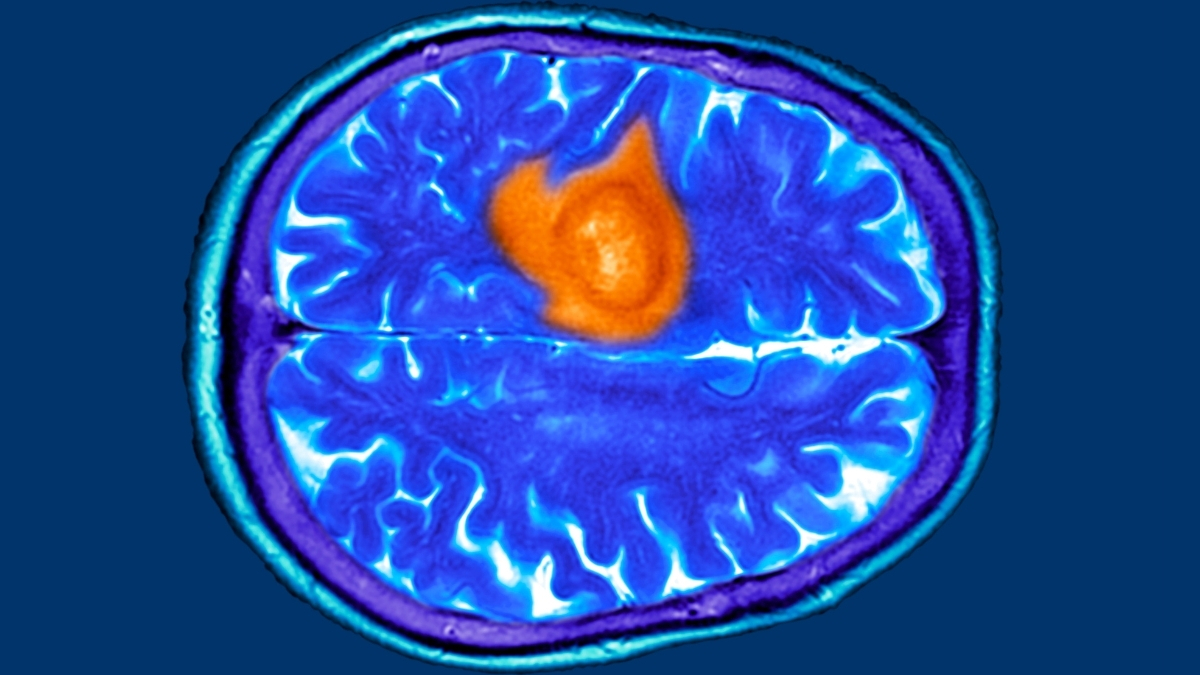

Glioblastoma survivor defies odds with ultrasound-assisted therapy

Becca Valle’s migraines led to a glioblastoma diagnosis. After tumor removal, she joined a focused ultrasound trial to temporarily open the blood-brain barrier to boost chemotherapy. In 34 participants, the approach showed a survival advantage, with up to 40% alive longer than expected; Valle has no evidence of disease four years later and says she’s living life to the fullest. The device and method are not yet FDA-approved and not widely available.